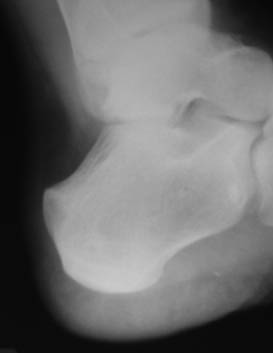

Хондропатия пяточной кости

Выкладываю снимки и томограммы левой пятки и контрлатеральную, здоровую. Пациенту 19 лет, беспокоят ноющие боли. Лечили блокадами и физиопроцедурами.Юрий Алексеевич Булахтин

Судя по снимкам, Stress fracture, случай редкий, но встречается, чаще у спортсменов. Лечение, как и все стрессовые переломы - костыли без нагрузки на больную ногу в течении 6 недель и упражнения на растяжение плантарной фасции и ахилла .

Больше похоже на плантарный апофизит (болезнь Севера). Обычно проходит самостоятельно по мере закрытия зон роста.

прошу прощения, я хотел сказать пяточный апофизит

Ну,во-первых,Ваш диагноз,как мне кажется,сомнений не вызывает.Можно трактовать и как неблагоприятный исход болезни Севера или Хаглунда.Суть не меняется,проблема чисто терминологическая.